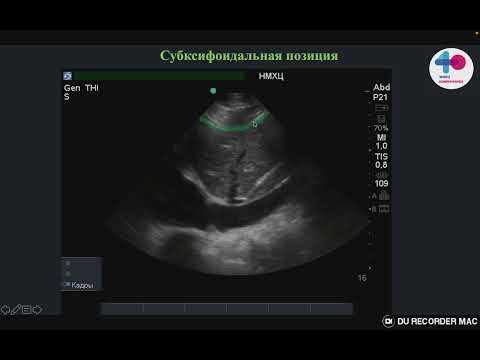

HOW TO Мониторинг волемического статуса, нижняя полая вена

VExUS ультразвуковой мониторинг венозного спланхнического кровотока